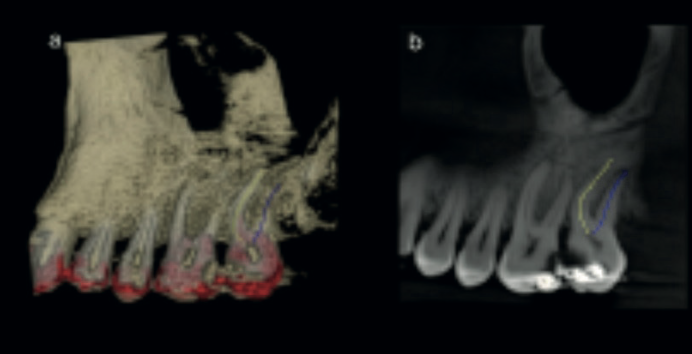

Fig. 1 — Diagnostic periapical radiograph alongside CBCT sagittal, coronal, and axial views revealing two canals in the palatal root of UL7

Fig. 1 (a) Diagnostic periapical radiograph. (b) Sagittal view of buccal roots. (c) Sagittal view of palatal root showing two canals. (d) Coronal view of palatal root. (e) Axial view confirming two separate palatal canals.